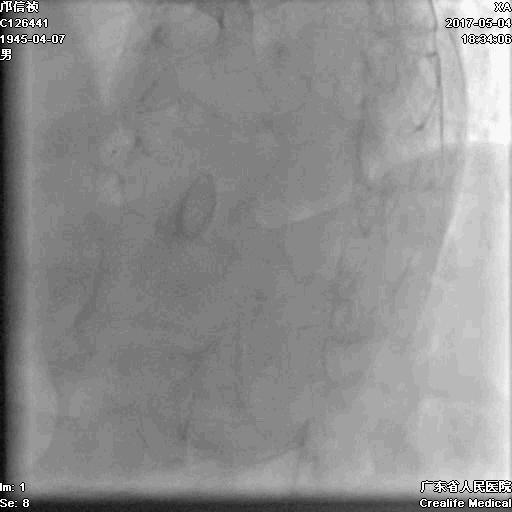

第二步:处理LCX

Fielder XT-A,Gaia First ---在微导管支撑下通过闭塞病变

LCX植入支架

2.0*10mm球囊

2.75*22mm药物支架